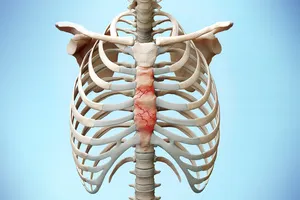

12. 늑골 골절

갈비뼈가 부러지면 숨을 쉴 때마다 찌릿찌릿한 통증이 느껴지고, 깊게 숨을 쉬기가 힘들어집니다. 통증을 줄이는 약을 먹고 충분히 쉬는 것이 중요하며, 경우에 따라 수술이 필요할 수도 있습니다.